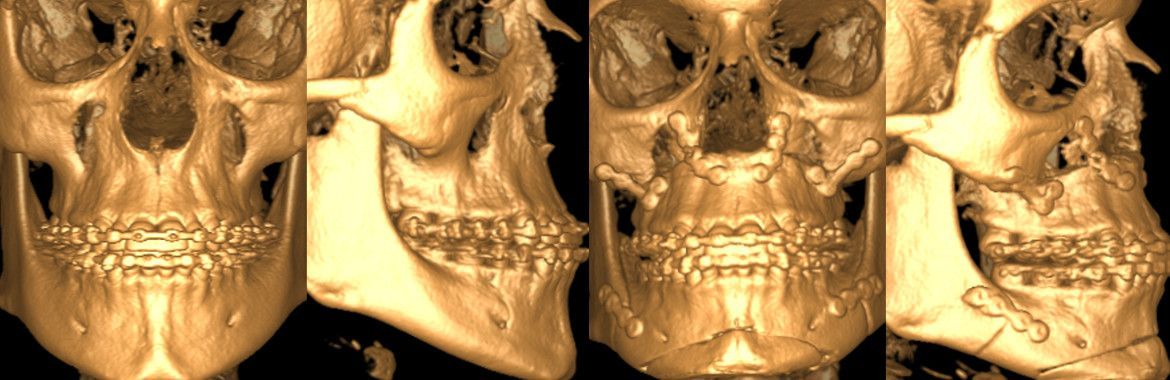

Traumatologie

Behandlung von Weichteilverletzungen/ Frakturen im Mund-, Kiefer-, Gesichtsbereich ambulant in der Praxis oder im Rahmen der Belegarzttätigkeit am Spitalzentrum Biel in Narkose.

- Unterkieferfrakturen

- Mittelgesichts-, Augenbodenfrakturen